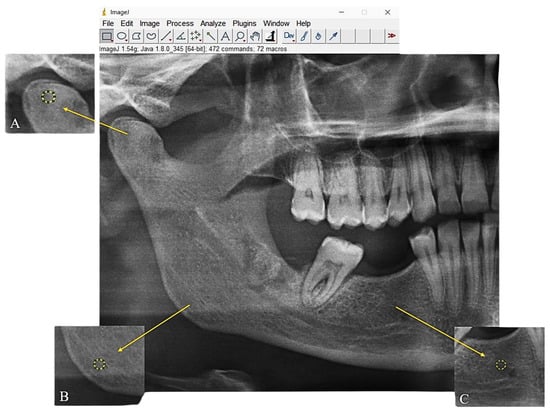

- ROI-1: A 30 × 30-pixel circular region located at the geometric center of the right mandibular condyle.

- ROI-2: A 30 × 30-pixel circular region positioned at the geometric center of the right mandibular angle.

- ROI-3: A 30 × 30-pixel circular region located in the right mandibular molar area (Figure 1).